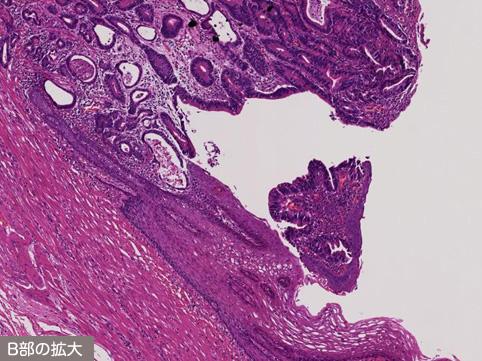

Criteria of Hist.ClassificationMalignant epithelial tumor/Adenocarcinoma

Macroscopic TypesType 0/IIc (IIc+IIa) Superficial depressed and elevated type

Depth of Tumor Invasionsubmucosa